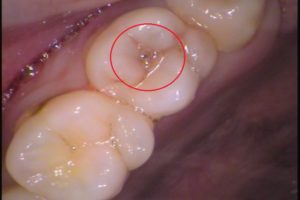

赤丸で囲まれたここです。

実際には、レントゲン撮影で虫歯の進行状態を把握しています。